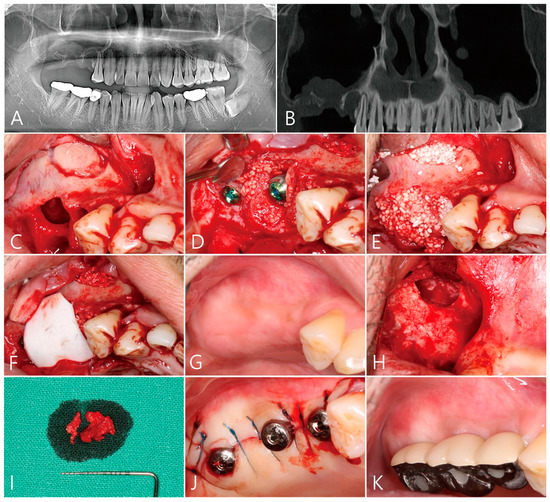

Patient 1 is a 49-year-old male smoker with no systemic diseases that would affect the operation. On the right maxilla, posterior teeth were extracted due to periodontal disease (Table 1). Some sinus floor defects and thickening of the maxillary sinus membrane were observed on the panoramic radiograph and on the CBCT which were taken two months after the extractions were completed (Figure 1A,B).

After the flap was reflected, the granulation tissue in the extraction socket was thoroughly removed. The defect in the buccal root area was severe. A lateral bone window was prepared for sinus floor elevation (Table 1, Figure 1C). The maxillary sinus bone graft was performed using Osteon III (Genoss, Suwon, Korea) and three implants (Ø 4.3 × 10 mm Implantium, Dentium, Suwon, Korea) were placed (Figure 1D). The residual peri-implant defect was additionally filled with bone graft material (Figure 1E). The bone graft site was covered with a resorbable collagen membrane (Genoss, Suwon, Korea) and the flap was closed (Figure 1F). Postoperative clinical symptoms were not significantly different from those of general maxillary sinus surgery patients. Clinically, 6 months after the operation, there was no wound exposure and the healing was uneventful (Figure 1G). The uncovering procedure was performed under local anaesthesia. To remove the large grafting void, the mucoperiosteal flap was sufficiently reflected buccally, and then the graft void was removed using the #15 Bard-Parker blade and periodontal curettes (Figure 1H). The specimen did not separate cleanly from the surrounding tissues (Figure 1H). The grafting void and surrounding tissues were fibrotic (Figure 1I). The removed specimens were fixed in 10% formalin for biopsy. After debridement around the grafting void, no additional bone grafting was performed. This is because the shape of the defect contained a 3-walled osseous housing. After insertion of the healing abutment, the flap was closed (Figure 1J). After 2 months, the prosthesis was delivered (Figure 1K).

Figure 1. Case 1. (A) Preoperative panoramic radiography. A severe defect is present in the maxillary right posterior extraction socket, and the height of the residual bone is low; (B) panoramic image of CBCT taken preoperatively. A compromised extraction socket is observed in the right maxillary sinus, and the maxillary sinus membrane is thickened; (C) after the flap was reflected, the granulation tissue in the extraction socket was thoroughly removed. The buccal bone defect was severe. A lateral bone window was prepared for sinus floor elevation; (D) the maxillary sinus bone graft using synthetic bone graft substitute was performed and two implants were installed; (E) the peri-implant defect was additionally filled with a bone graft substitute; (F) resorbable collagen membrane was used to cover the grafting material and the flap was closed; (G) clinical findings 6 months after surgery. Healing was uneventful; (H) After the flap was reflected, the graft void was removed; (I) the removed specimen which was not clearly separated from the surrounding tissue; (J) after insertion of the healing abutment, the flap was closed; (K) Clinical appearance after delivery of the prosthesis.